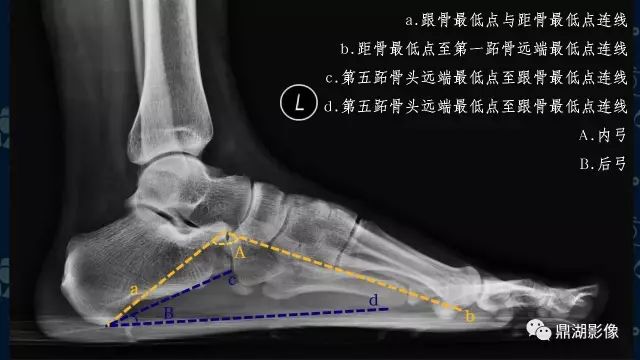

影像检查

辅助检查方法主要是X线检查,应负重条件下摄足正侧位X线片,主要在足侧位片测量足弓的角度改变。